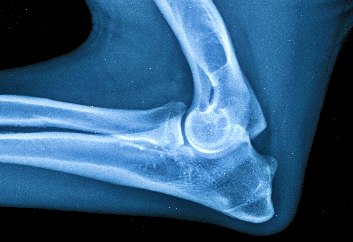

RTG DLK - Zdravý lakeť - Large Skeletal 25-45 kg Elbow LAT

Diagnostika DLK prebieha röntgenologicky tzn. RTG vyšetrením vykonanom v celkovej anestéze na oficiálne schválenom RTG pracovisku, prípadne na CT (computed tomography). U nás zvyčajne spočíva v zhotovení RTG snímok lakťa ideálne z 2 projekcií (bočnej a predo-zadnej s 15°pronáciou).  Od 12 týždňov veku je možné vykonať tzv. rannú diagnostiku. V prípade podozrenia na dyspláziu sa diagnostika vykonáva ihneď bez ohľadu na vek. Pre účely chovnosti je jedinec vyšetrovaný po dosiahnutí určitého veku v závislosti od plemena od 12,18 či 24 mesiacov.

Diagnostikovať UAP vo veku 4 – 5mesiacov je predčasné. Obvykle je možné určiť diagnózu s klinickými príznakmi od veku 6 – 12 mesiacov. FCP sa vyskytuje od 4 do 10 mesiacov veku. Na rozdiel od UAP, FCP nemusí byť viditeľná rádiograficky. Diagnóza FCP je typická zo sekundárnych degeneratívnych zmien vyplývajúcich z abnormality, ktoré sa dajú určiť od veku 7 – 8 mesiacov.